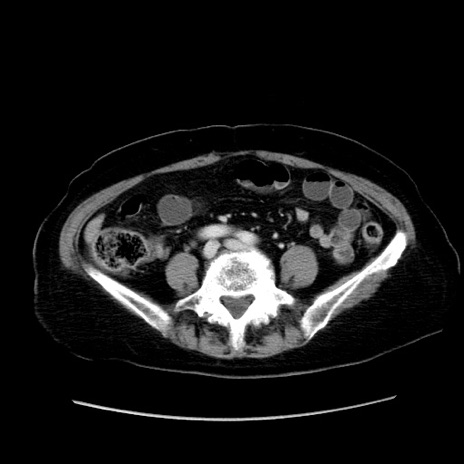

症例19(横断像)

【症例】80歳代女性

【主訴】下腹部痛

【現病歴】約8時間前より下腹部痛の出現あり、救急外来受診。

【既往歴】両側付属器切除

【身体所見】意識清明、下腹部正中に手術痕あり、その部位に一致して圧痛と反跳痛あり。腸蠕動音は亢進。

【データ】WBC 9300、CRP 0.15